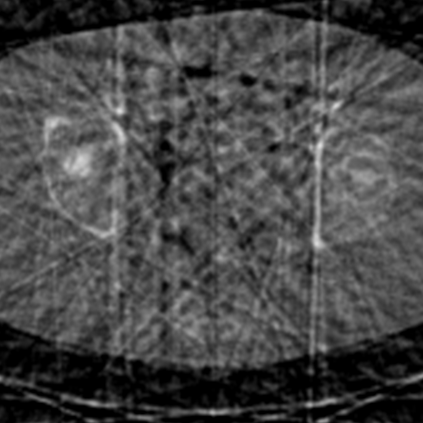

Sparse-view computed tomography (CT) -- using a small number of projections for tomographic reconstruction -- enables much lower radiation dose to patients and accelerated data acquisition. The reconstructed images, however, suffer from strong artifacts, greatly limiting their diagnostic value. Current trends for sparse-view CT turn to the raw data for better information recovery. The resultant dual-domain methods, nonetheless, suffer from secondary artifacts, especially in ultra-sparse view scenarios, and their generalization to other scanners/protocols is greatly limited. A crucial question arises: have the image post-processing methods reached the limit? Our answer is not yet. In this paper, we stick to image post-processing methods due to great flexibility and propose global representation (GloRe) distillation framework for sparse-view CT, termed GloReDi. First, we propose to learn GloRe with Fourier convolution, so each element in GloRe has an image-wide receptive field. Second, unlike methods that only use the full-view images for supervision, we propose to distill GloRe from intermediate-view reconstructed images that are readily available but not explored in previous literature. The success of GloRe distillation is attributed to two key components: representation directional distillation to align the GloRe directions, and band-pass-specific contrastive distillation to gain clinically important details. Extensive experiments demonstrate the superiority of the proposed GloReDi over the state-of-the-art methods, including dual-domain ones. The source code is available at https://github.com/longzilicart/GloReDi.